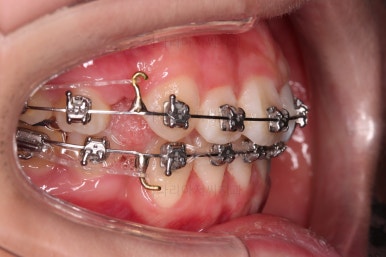

적절한 시기에 발치를 하고요.

치열이 우선 가지런해졌다면 미니스크류를 이용해서 앞니를 뒤로 당겨주게 됩니다.

조심스럽게 앞니를 뒤로 뒤로 당겨줍니다.

이번 환자분은 특히나 옥니가 되지 않도록 매우 주의해야 하는 경우였고, 아래 턱끝 힘이 센 분이기 때문에 아래 앞니가 옥니가 될 가능성이 매우 큰 분이었어요.

윗니는 당겨넣을 양이 아직 많고, 아랫니는 앞니 각도 조절(옥니가 되지 않게)을 매우 다양한 테크닉으로 해 나갑니다.